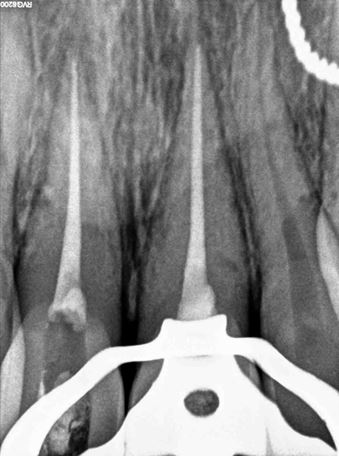

Management of intrinsic discoloration using walking bleach technique in maxillary central incisors

Introduction. Non-vital bleaching is a non-invasive technique to treat the intrinsic discoloration of teeth of several etiologies. Hydrogen peroxide and sodium perborate are commonly used bleaching agents.

Method. Maxillary central incisors were isolated with rubber dam and root canal treatment was performed. Barrier space preparation was done using a heated instrument. Glass ionomer cement was used a barrier material. Mixture of hydrogen peroxide and sodium perborate was placed in the canal and sealed with intermediate restorative material. After 1 week, the procedure was repeated to achieve the desired results.